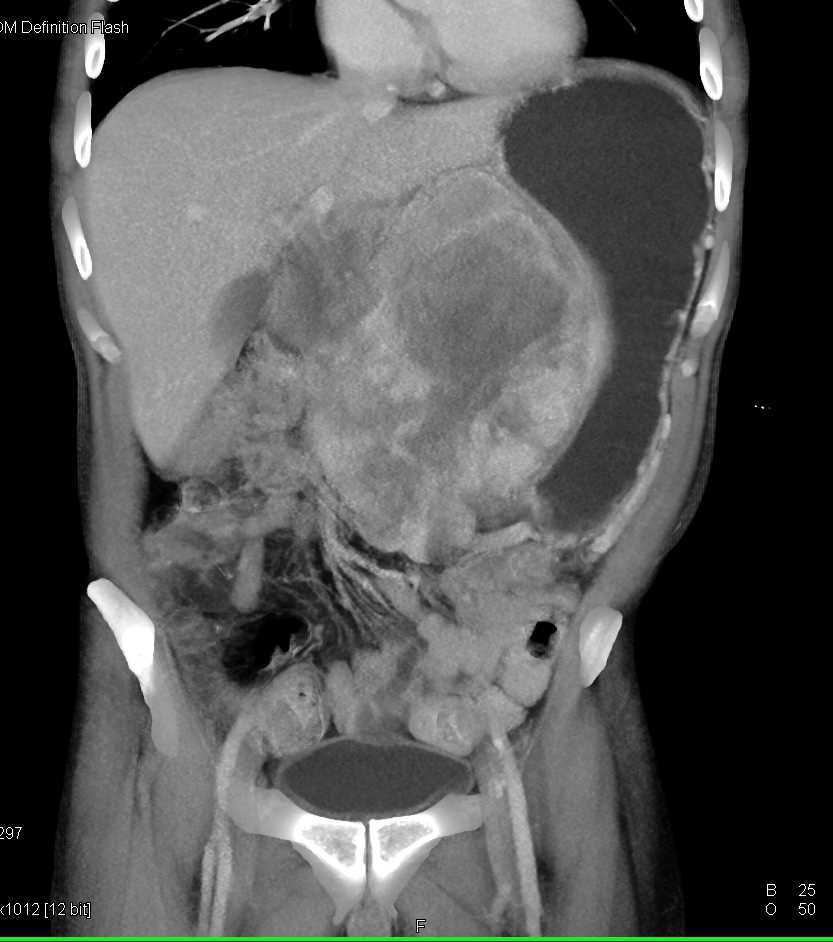

Lagre Gastric GIST Tumor